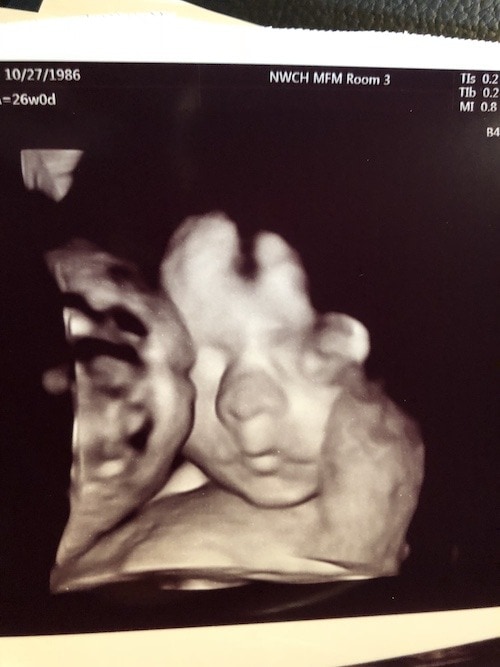

Ultrasound Photos at 26 Weeks Pregnant With Twins